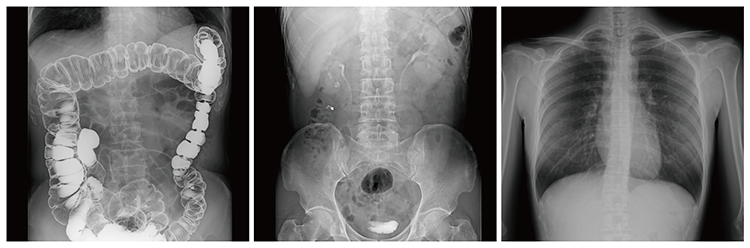

რენტგენი – საუკეთესო მეთოდი ძვლებისა და ქსოვილების მდგომარეობის შესაფასებლად

რენტგენი ასევე არის ერთ-ერთი ყველაზე მნიშვნელოვანი და გავრცელებული დიაგნოსტიკური პროცედურა, რომელიც სამედიცინო პრაქტიკაში გამოიყენება ძვლებისა და ქსოვილების მდგომარეობის შესაფასებლად. ეს პროცედურა გთავაზობთ სწრაფ, ზუსტ და უსაფრთხო მეთოდს, რათა ექიმმა შეძლოს პაციენტის პრობლემების დროულად გამოვლენა და სწორი მკურნალობის გეგმის შემუშავება.რენტგენი არის აუცილებელი როგორც სერიოზული ტრავმების, ისე პროფილაქტიკური შემოწმებების დროს. იგი საშუალებას აძლევს ექიმს დაინახოს ისეთი დეტალები, რომელიც სხვა მეთოდებით შესაძლოა შეუმჩნეველი დარჩეს.

ბოჭორიშვილის კლინიკაში წარმოდგენილია რენტგენის Shimadzu FLEXAVISION F4 აპარატი - მაღალი ტექნოლოგიური, მრავალფუნქციური რენტგენული სისტემა, რომელიც აერთიანებს ფლუროსკოპიას და რადიოგრაფიას ერთ აპარატში. მისი ინოვაციური Flat-Panel Detector (FPD) უზრუნველყოფს ფართო ხედვასა და მკაფიო გამოსახულებას

FLEXAVISION F4-ის უპირატესობები:

- სიზუსტე – დეტალურად აჩვენებს ძვლების, სახსრების და ქსოვილების სტრუქტურას, რაც საშუალებას აძლევს ექიმს დროულად შეაფასოს ნებისმიერი პრობლემა;

- სწრაფი პროცედურა – შედეგები ხშირად დაუყოვნებლივ მიიღება, რაც მნიშვნელოვნად ამარტივებს დიაგნოსტიკის და მკურნალობის პროცესს;

- უსაფრთხოება – თანამედროვე აღჭურვილობა უზრუნველყოფს მინიმალურ რადიაციას, რაც ხელს უწყობს პროცედურის უსაფრთხოებას, როგორც ზრდასრულებისთვის, ასევე ბავშვებისთვის;

- უნივერსალურობა - რენტგენი უსაფრთხო და ეფექტურია სხვადასხვა ასაკის პაციენტებისთვის, დაწყებული ბავშვებით და დასრულებული უფროსი ასაკის ადამიანებით.

როგორ მუშაობს რენტგენი FLEXAVISION F4?

FLEXAVISION F4 იყენებს სპეციალურ რადიაციას, რომელიც სხეულში აღწევს და ქმნის სურათს ქსოვილების ან ძვლების სტრუქტურის შესახებ. პროცედურა სრულდება რამდენიმე ეტაპად:- პაციენტის მომზადება - ექიმი აუხსნის პაციენტს პროცედურის მიზანს და ყველაფერს, რაც საჭიროა მის მოსამზადებლად. ზოგჯერ საჭიროა რომ პაციენტმა მოიხსნას სამკაულები ან მოიშოროს ტანსაცმელი, რომელიც აფერხებს სურათის გადაღების პროცესს;

- სურათის გადაღება - პაციენტი დგება ან წვება სკანერის წინ, ხოლო სპეციალური აპარატი იღებს სურათს;

- სურათის ანალიზი - მიღებული გამოსახულება ექიმს საშუალებას აძლევს დეტალურად შეაფასოს ძვლები, სახსრები და ქსოვილები, გამოავლინოს ტრავმები ან დაავადებები;

- მკურნალობის გეგმის შემუშავება - რენტგენის შედეგების მიხედვით ექიმი ადგენს საჭირო მკურნალობის გეგმას, ფიზიოთერაპიას ან ითხოვს დამატებით კვლევებს.

რენტგენის პრაქტიკული მნიშვნელობა

რენტგენი არის ეფექტური არა მხოლოდ ტრავმების შესაფასებლად, არამედ ჯანმრთელობის მდგომარეობის გრძელვადიანად კონტროლისთვის. მისი დახმარებით შესაძლებელია:- ძვლების, სახსრების და ზოგიერთი რბილი ქსოვილის მდგომარეობის შეფასება;

- ართრიტის, ოსტეოპოროზის ან სხვა ქრონიკული პრობლემების გამოვლენა;

- ხერხემლის შეფასება, მათ შორის ფუნქციური დატვირთვის დროს;

- ტრავმების და გამოჯანმრთელების პროგრესის კონტროლი;

- ფილტვების და გულის მდგომარეობის შეფასება;

- ცხვირის დანამატი ღრუების (სინუსების) გამოკვლევა;

- კუჭ-ნაწლავის ტრაქტის გარკვეული პათოლოგიების შეფასება;

- შარდ-სასქესო სისტემის გამოკვლევა.